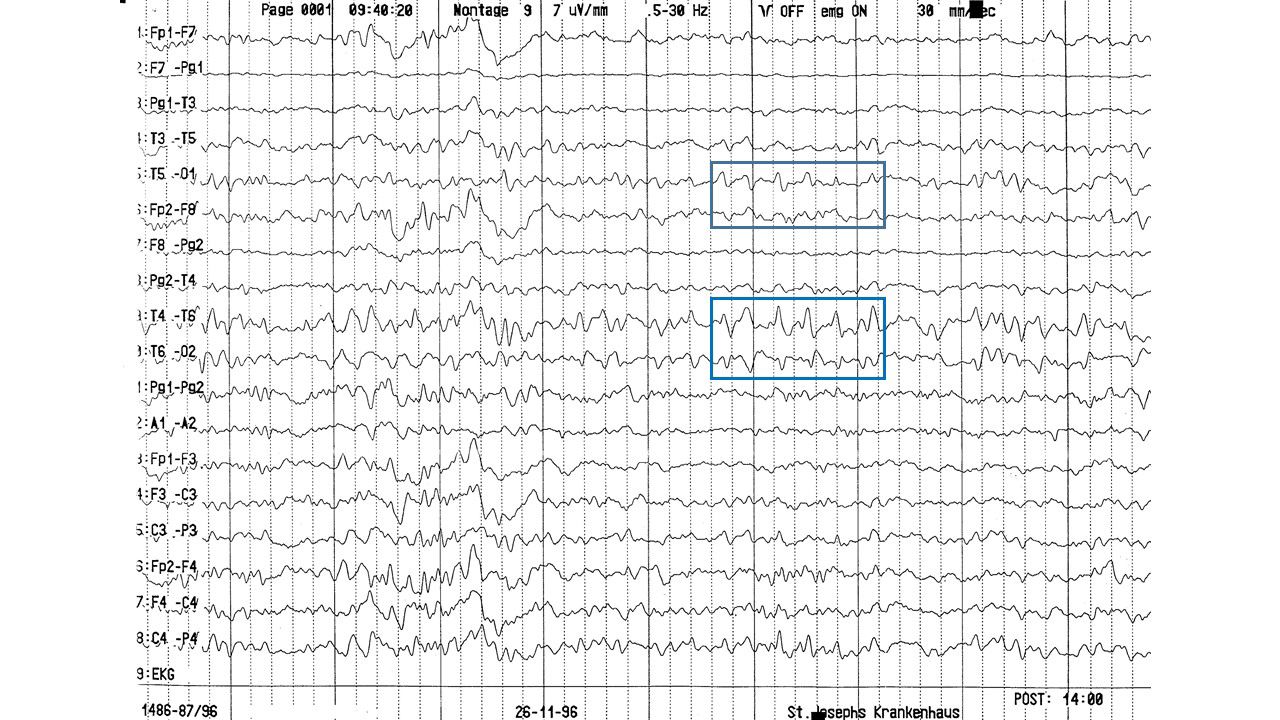

EEG-Seminar I | 23.40 zurück | weiter

folie632.jpg